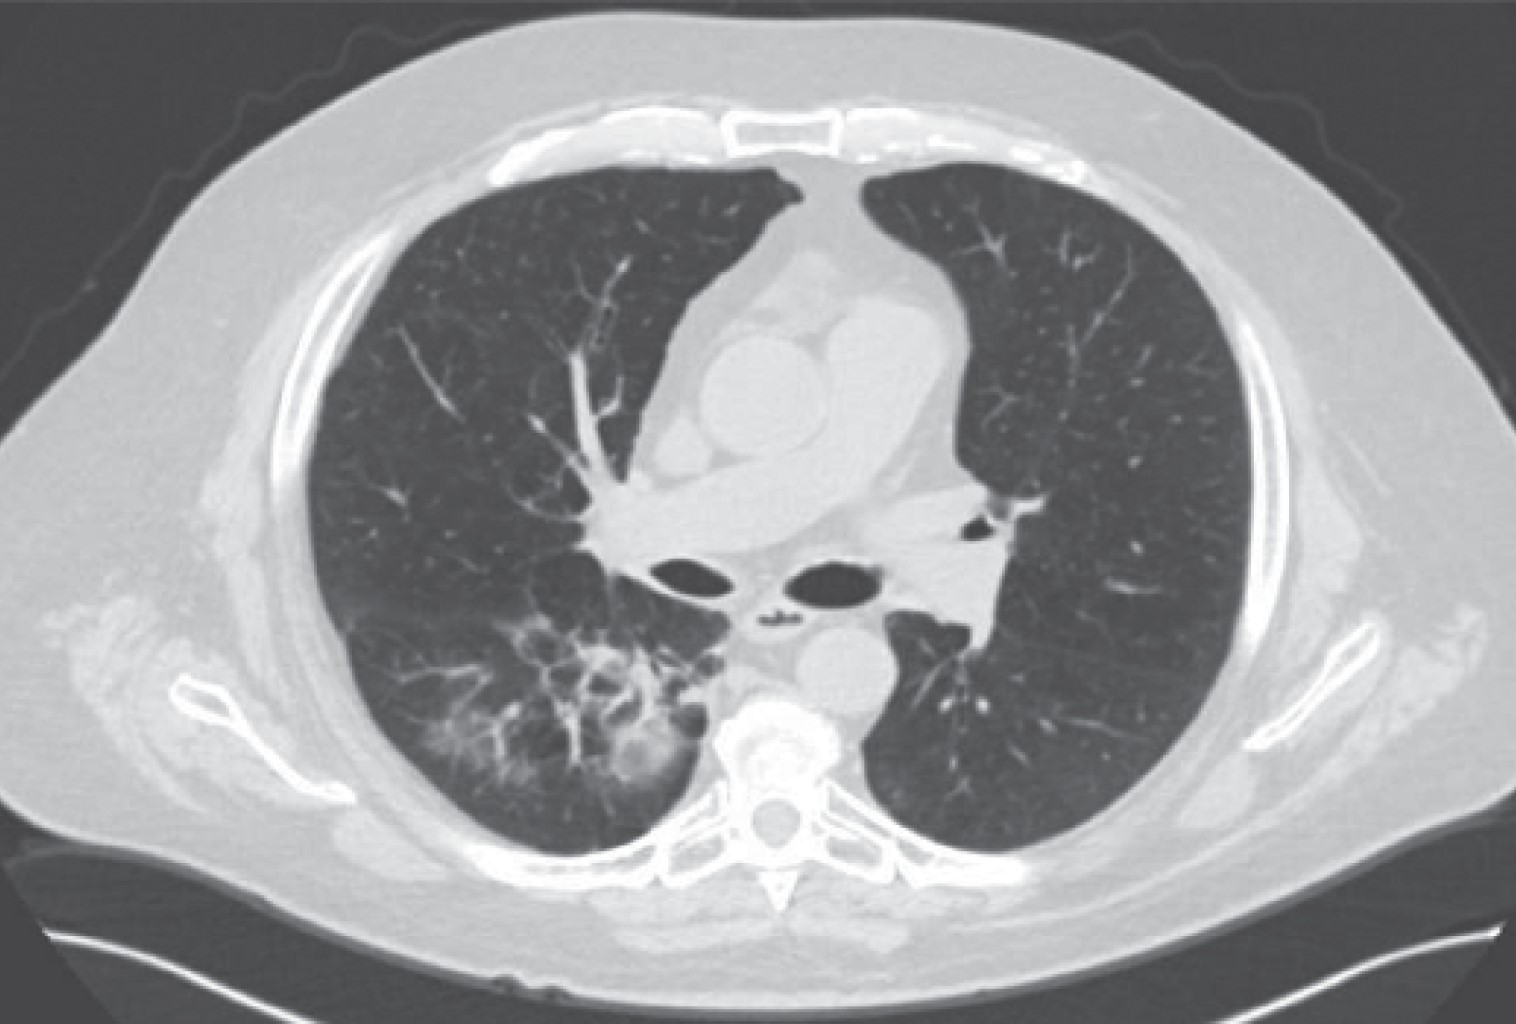

Metachronous lung cancer in a patient with a history of kidney cancer requiring bronchial stent placement. Case report and literature review

The appearance of a multiple primary malignant neoplasms is more frequent in elderly patients, lung cancer is the leading cause of cancer death worldwide, the frequency of synchronous and metachronous lung cancers has increased in recent years due to advances in early detection techniques, multiple malignancies can be classified as synchronous or metachronous according to the time of onset in relation to the first malignancie, synchronous those that appear in the first six months and metachronous as those that appear after six months. We present the case of a 66-year-old male patient with a history of right radical nephrectomy for clear cell renal cancer, who goes to the emergency department seven years later for respiratory symptoms and hemoptysis. In his study protocol, he is diagnosed with a parahiliary right upper lobe endobronchial tumor of epidermoid lineage involving the right bronchus.

Figure 1